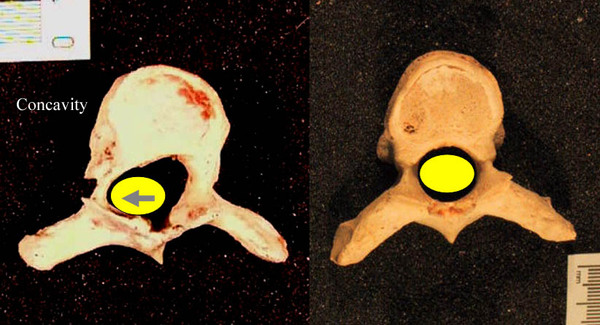

Сколиоз – это многоплоскостная деформация. Суть в чем, в норме наш позвоночник имеет изгибы в сагиттальной плоскости: шейный и поясничный лордоз, грудной кифоз.

При сколиозе эти изгибы уменьшаются (изменение в сагиттальной плоскости), появляются сколиотические дуга/дуги (изменение фронтальной плоскости).

Но это не все, позвонки в зоне деформации (изменение в аксиальной плоскости) сворачиваются своей центральной частью внутрь, а задними элементами наружу (торсия). На картинке ниже справа нормальный позвонок, а слева измененный позвонок, желтая точка – проекция спинного мозга в позвоночном канале.

Эта ротация изменяет строение позвонков. Если гипотетически взять и распрямить позвоночник, не фиксируя его ничем, то он вновь скрутиться из-за измененной анатомии.

Из-за торсии происходит скручивание грудной клетки (ребра прикрепляются к позвонкам), появляется реберный горб.